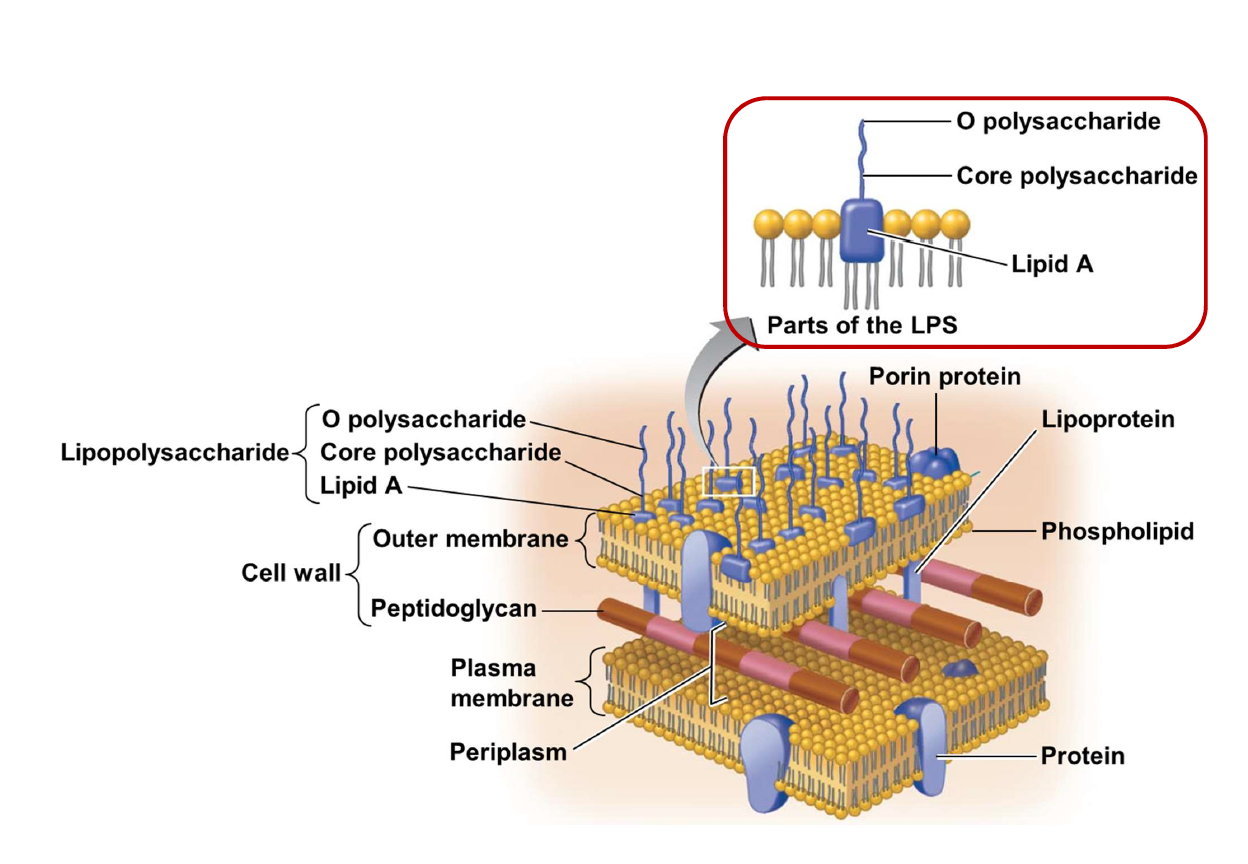

- Lipopolysaccharide (LPS)

- Lipid A 致病

- Core 含2-keto-3-

deoxy-octanoate(KDO)

格蘭氏染色

Negative

- 雙層膜

- Lipopolysaccharide (LPS)

- Peptidoglycan

Endotoxin

A.K.A Lipopolysaccharide (LPS)

- 可活化血小板及凝血系統為革蘭氏陰性菌造成敗血症的主因

Enterobacteriaceae (腸桿菌科, G-)

- LPS 長一根 O antigen, Lipid A都是抗原